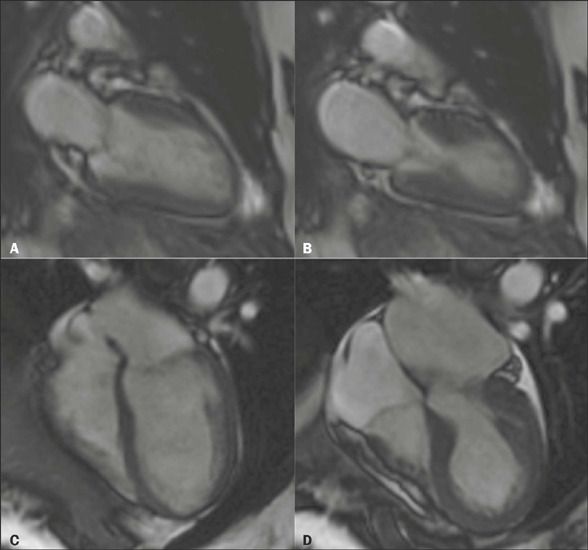

Takotsubo cardiomyopathy is an important differential diagnosis for acute chest pain. Imaging tests, such as ventriculography, echocardiography, computed tomography of the heart, and cardiac magnetic resonance, are valuable tools for diagnostic confirmation in this context. This study reviews the literature and exemplifies the spectrum of typical and atypical cardiac magnetic resonance findings in this disease, on the basis of the experience of our facility. Recognition of these characteristics underscores the roles that radiologists and cardiologists play in the care of patients with acute chest pain, enabling an accurate diagnosis and appropriate treatment.